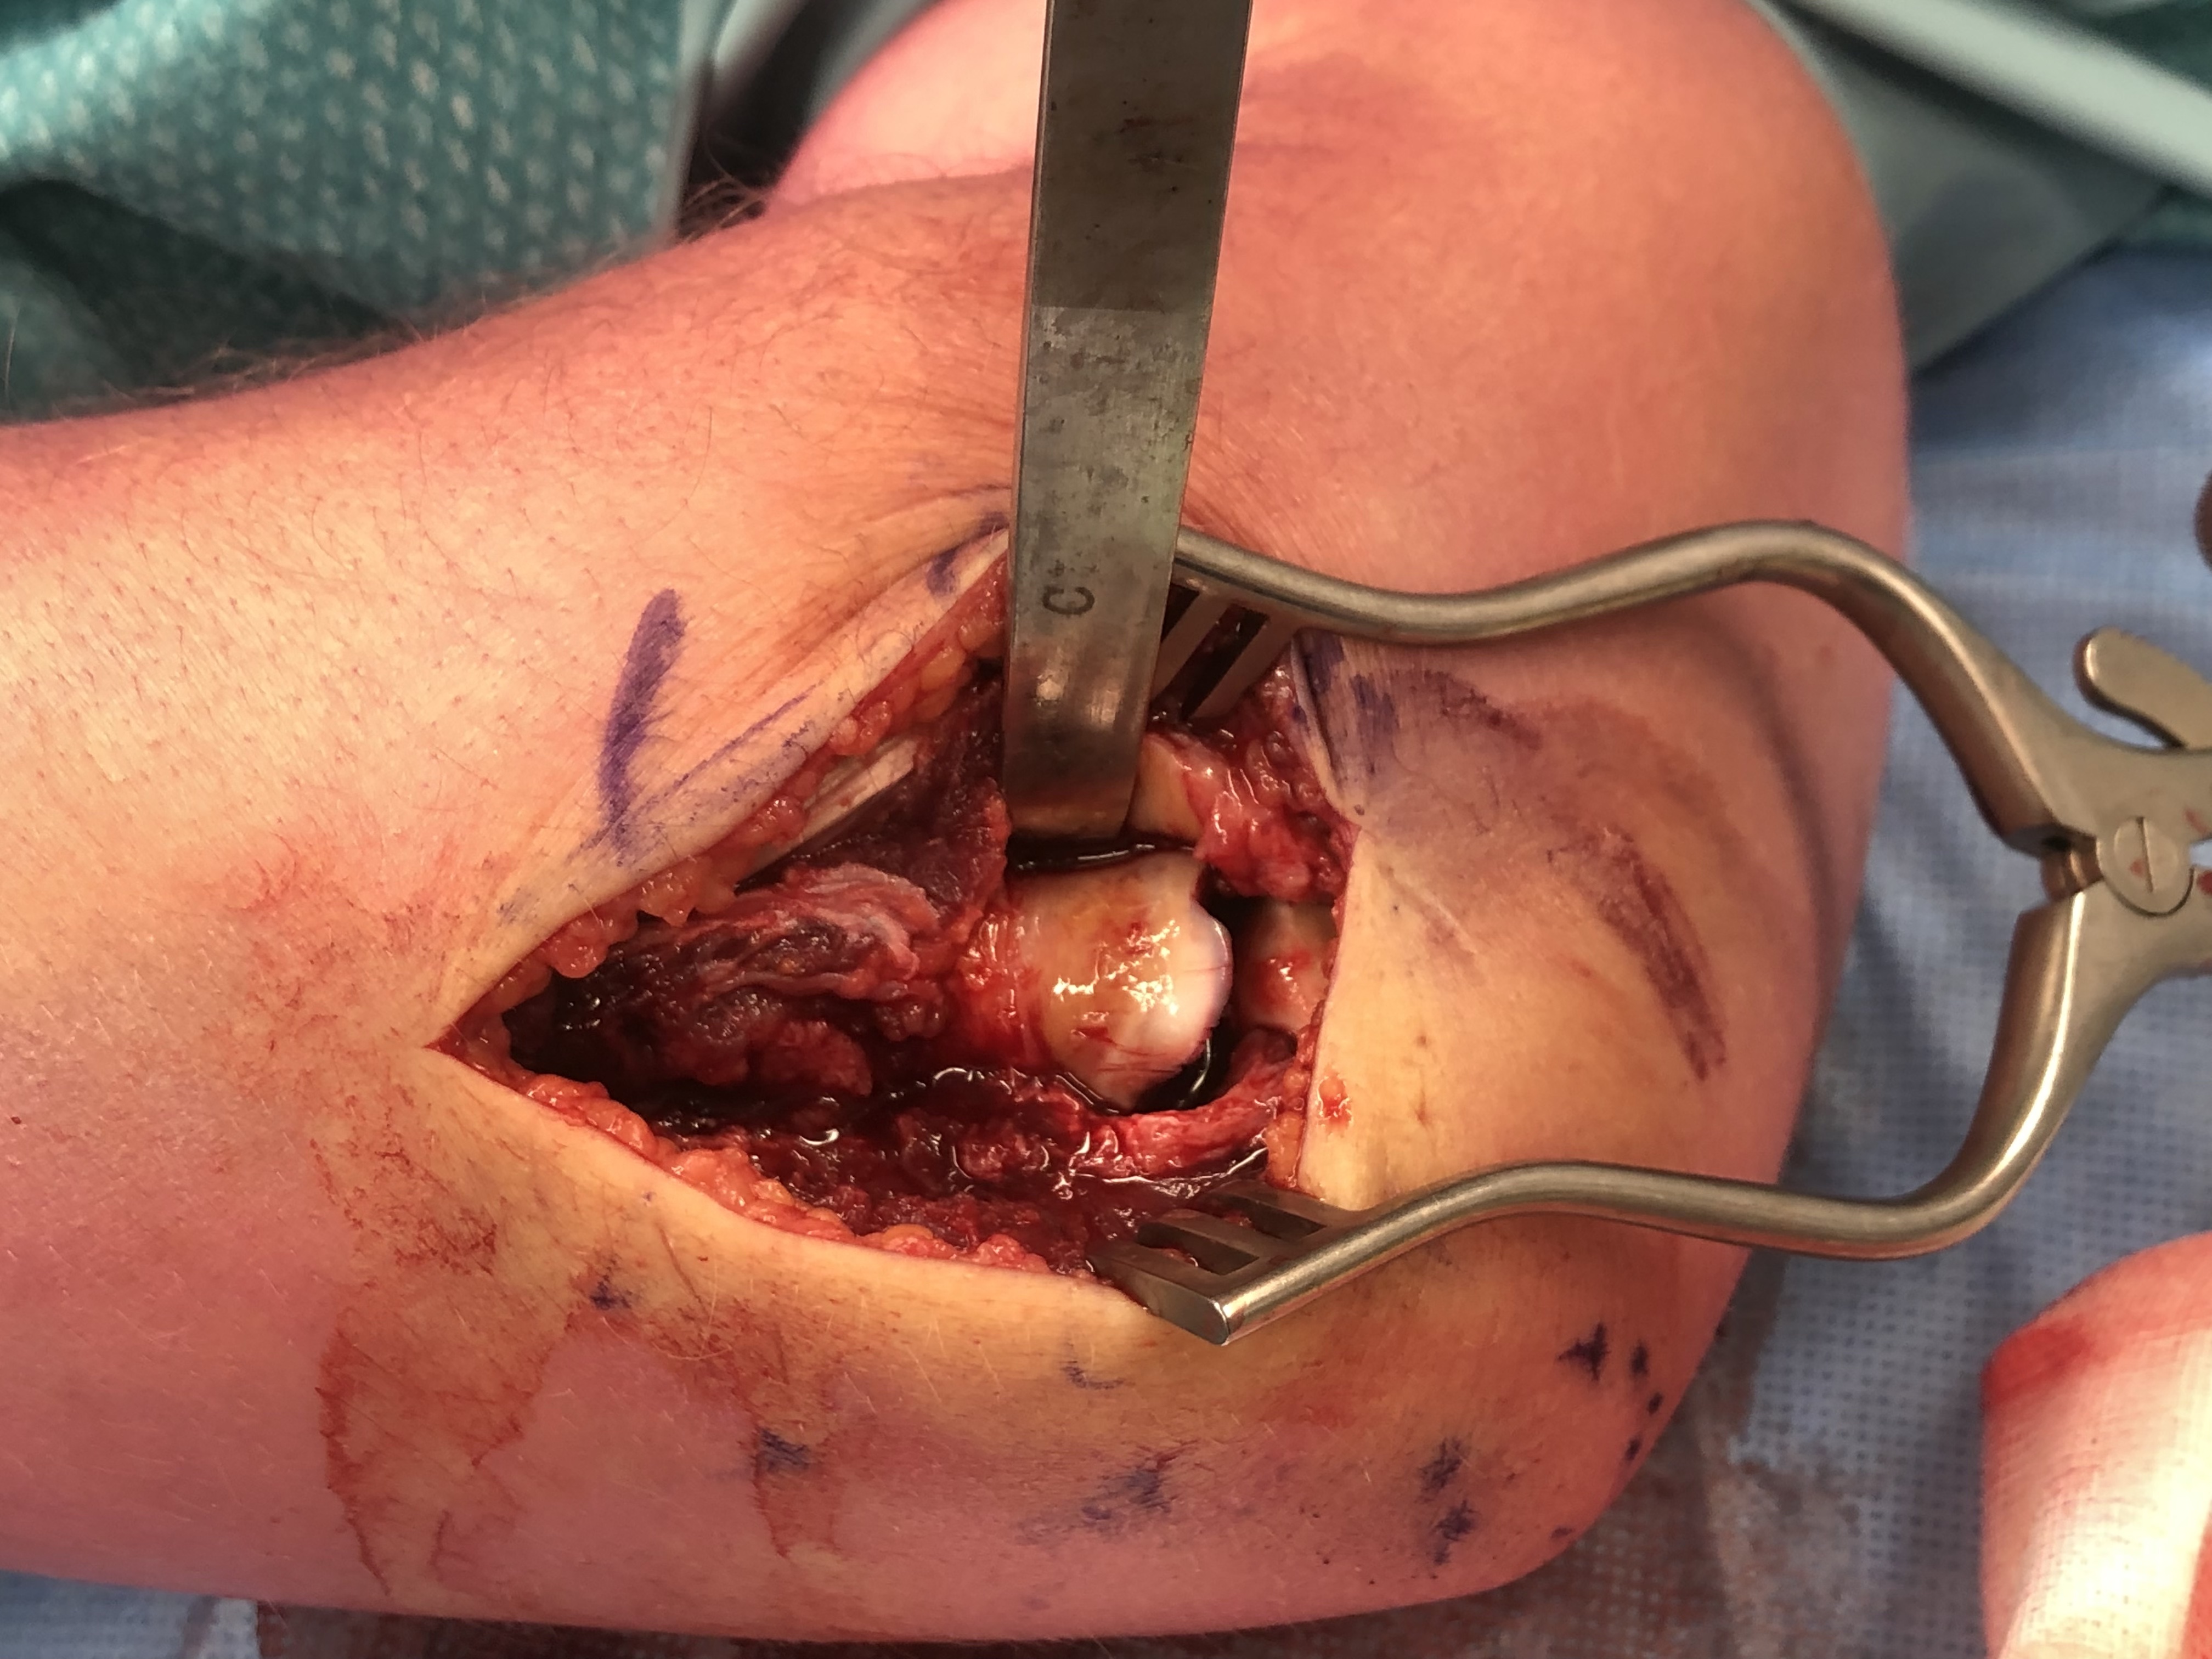

Radial Head Fixation

Technique

Kocher / Kaplan approach

- dissect muscles off capsule

- divide capsule in line with incision / create anterior and posterior flaps

- pronate forearm to protect PIN

- no Hohmann retractors anteriorly and limit distal dissection

- reduce fracture

Identify safe zone for implants

- posterolateral portion of cartilage / yellow and thinner, non articulating cartilage

- 90o arc between radial styloid and Lister's tubercle

- 2.5 or 3.5 headless compression screws